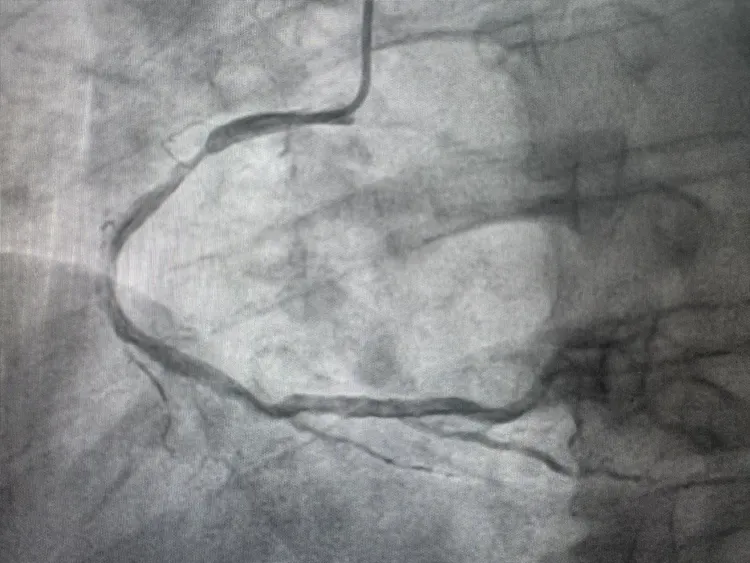

68岁的邵先生患有多年冠心病,反复胸闷、心绞痛,冬季及劳累后症状频发,严重影响生活。春节前夕,邵先生因心绞痛急性发作被紧急送至我院心内科,冠脉造影显示其多支血管病变,前降支为慢性闭塞病变,右冠脉近段狭窄达90%,病情十分危重。

↑第一次造影示右冠脉近段严重狭窄